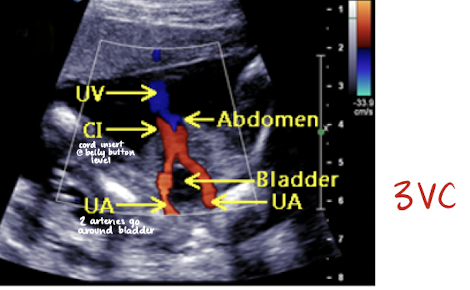

umbilical arteries

2 umbilical arteries carry deoxygenated blood from fetus to placenta

umbilical arteries can be noted on either side of bladder at fetal insertion

umbilical vein

1 umbilical vein carries oxygenated blood from placenta to fetus

umbilical cord color Doppler

color Doppler is used to visualize umbilical arteries and vein

the bladder, when full, is seen between 2 umbilical arteries

umbilical cord should be images in cross section and with color Doppler at level of bladder to confirm the number of cord vessels